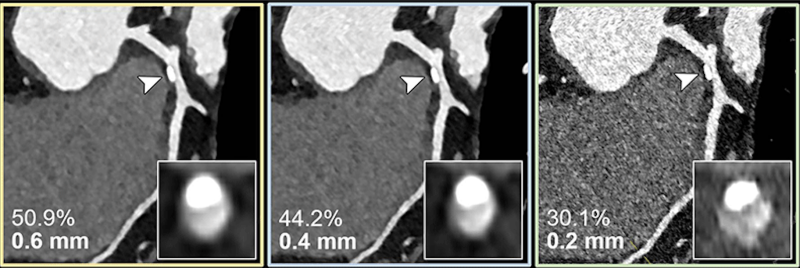

“The study used a combination of artificial vessel models and real-world patient data,” Dr. Emrich said. “It simulated three types of reconstructions from a single PCD-CT scan, resembling conventional CT, high-resolution, and ultrahigh-spatial-resolution scans. Observers evaluated the severity of stenosis and generated CAD-RADS classifications, guiding further patient management decisions.”

In-vitro results demonstrated a reduced overestimation of the stenosis by ultrahigh-spatial-resolution scans by reducing the adverse effects of the calcifications on the image.

Results from the patients with suspected or diagnosed coronary artery disease confirmed a lower median degree of stenosis for calcified plaques (29% vs. 42%) with ultrahigh-spatial-resolution PCD-CT compared to standard CT. Ultrahigh-spatial-resolution often led to patients being reclassified to a lower CAD-RADS category. Of the 114 patients, 54% were given a lower CAD-RADS classification than they were originally assigned. The researchers found in-vitro quantification of the 193 coronary CT angiography-based stenoses was also more accurate using ultrahigh-spatial-resolution than standard resolution.

Dr. Emrich explained that ultrahigh-spatial-resolution may address the current limitations of conventional cardiac CT angiography by reducing the overestimation of stenosis due to calcium blooming, an effect which can cause small, high-density structures—such as calcifications—to appear larger than their true size.